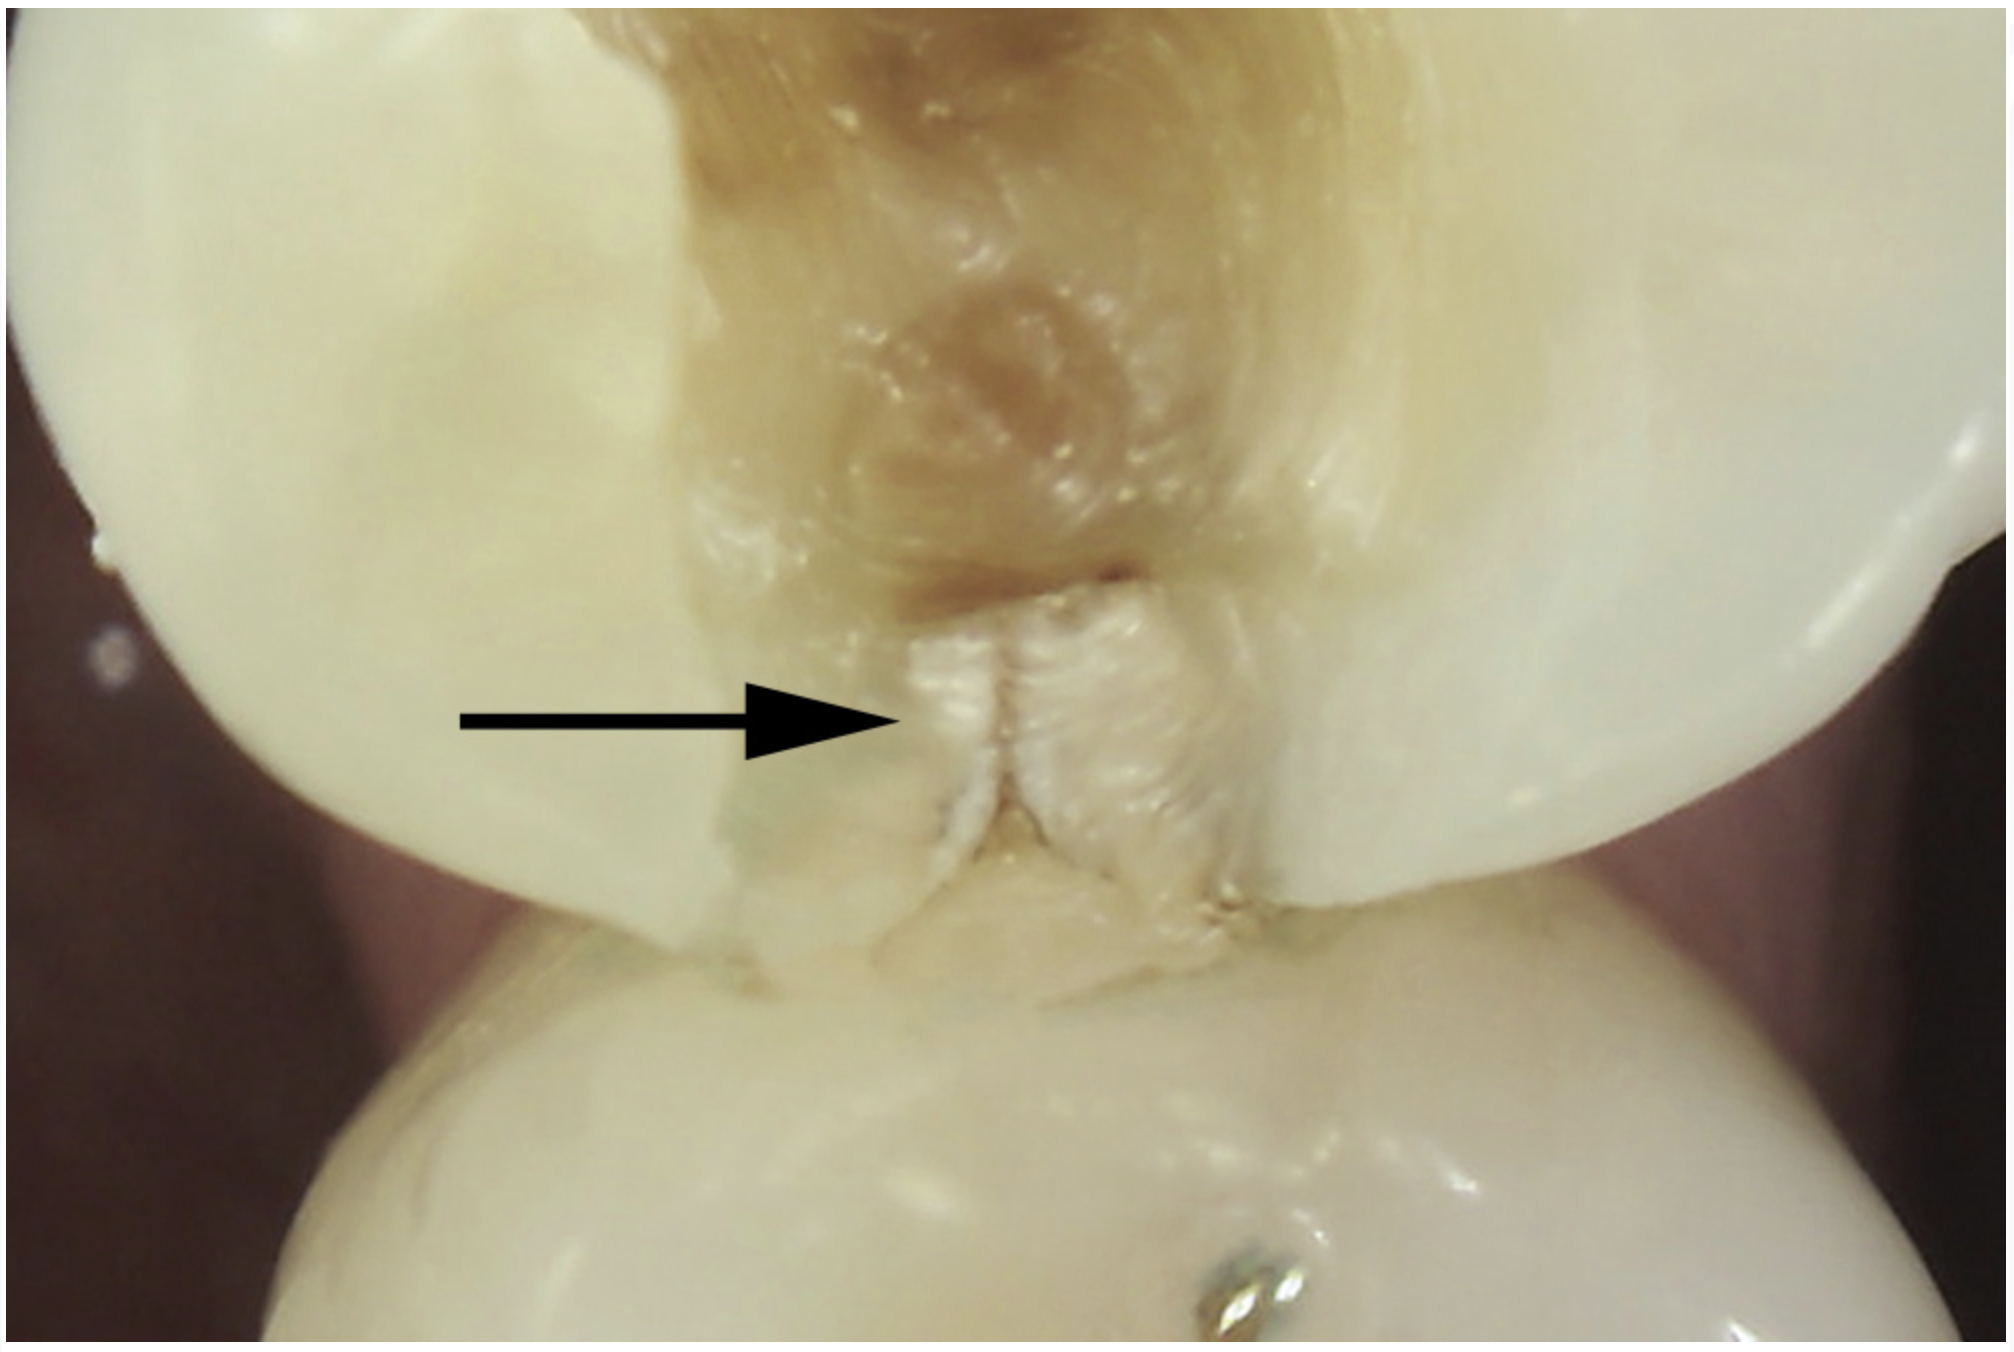

Transillumination

The use of fiber-optic transillumination for crack diagnosis is well documented in the literature.1-3,5,6,8-10,12,15-17,21-23 Teeth with significant cracks transilluminated with a fiber-optic light source will show a well-defined demarcation of blocked illumination at the crack lines, whereas structurally sound teeth will dissipate the light gradually throughout the tooth structure (Figure 3).22 While a variety of transillumination devices have been used to reveal cracks, pen-sized cordless units with a highly collimated light source and that are specifically manufactured for this purpose are ideal for this diagnostic technique. This is mainly because they emit the proper amount of light intensity to highlight cracks, and viewing can be done directly with the eye without using a protective device.22

Fig 3. Transillumination of an asymptomatic maxillary left second premolar blocked by an enamel marginal ridge crack (arrow) (mesio-occlusal view).

Figure 3